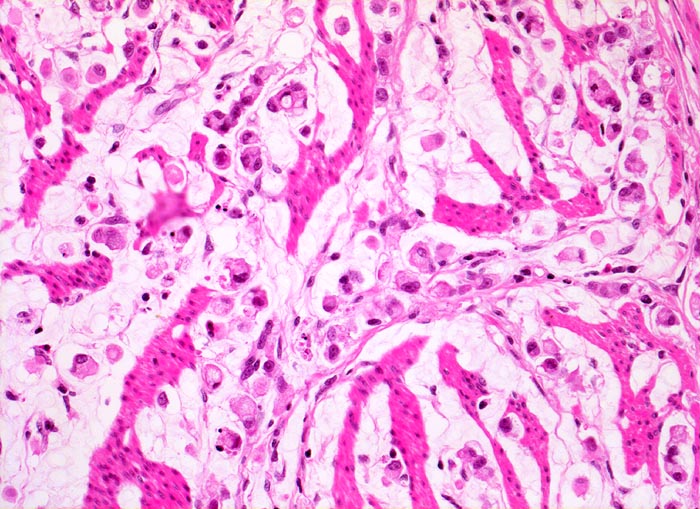

• Ein Grossteil des Tumorinfiltrats besteht aus einzeln oder in kleinen Gruppen liegenden Zellen mit intrazytoplasmatischen Schleimvakuolen, die teilweise den Kern verdrängen (Siegelringzellen): diffuser Typ des Magenkarzinoms nach Lauren.

• Nur vereinzelt Drüsenbildung.

• Lymphgefässeinbrüche.